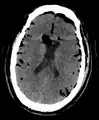

Large pneumocephaly secondary to surgical wound

Pneumocephaly